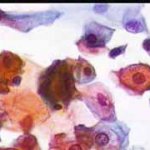

Papanicolaou: Πλακώδη επιθηλιακά κύτταρα κυρίως της επιφανειακήςστιβάδας, περίπου κατά50% και πλέον οξεόφιλα (16η ημέρα κύκλου!) . Ωστόσσο και αρκετά της διαμέσου και της παραβασικής, εν μέρει με διογκωμένους, ανισομεγέθειςαρραιοχρωματικούςδιαυγείςπυρήνεςKοιλοκυττάρωση.Η εικόνα συνηγορεί για δυσπλασία σοβαρού βαθμού.

Λόγω και του κολποσκοπικούευρήματος, μικροβιοψία που κατεδειξε ιστολογικώς CIN III